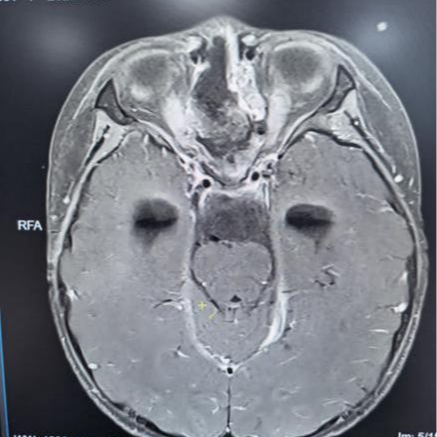

术前核磁共振检查

为精准掌握肿瘤情况,团队为欢欢完善了垂体MRI平扫+增强检查及相关激素水平检测。结果显示:肿瘤体积超过4厘米,形如鸡蛋,已严重压迫视神经与垂体,突入第三脑室,并与周围重要神经血管结构紧密粘连。颅咽管瘤是一种起源于颅底的先天性良性肿瘤,因体积大、位置深,且毗邻下丘脑、视神经、垂体等重要结构,手术切除难度极高,稍有不慎就可能导致失明、终身内分泌紊乱甚至有生命危险。